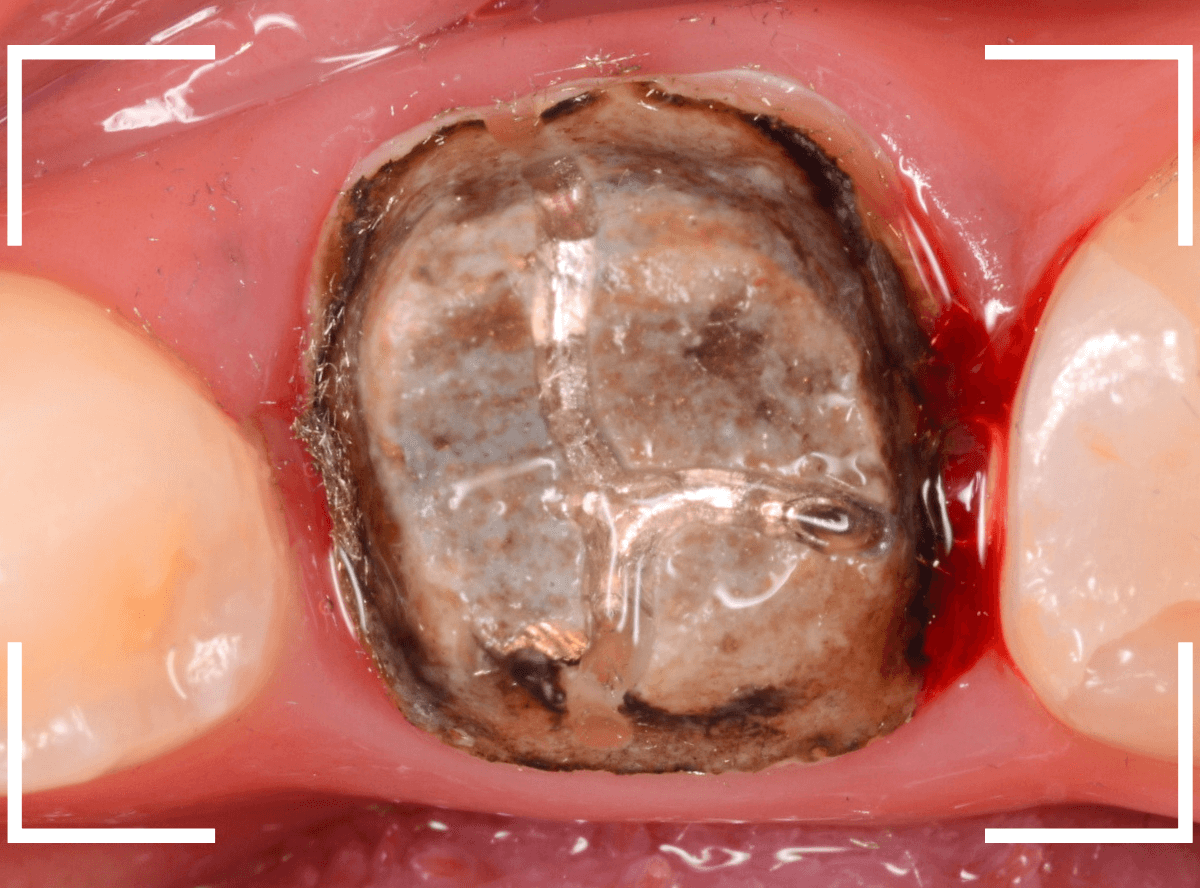

まずは、奥のメタル・クラウンを外します。

メタル・コアが入っていますが、こちらも慎重に外して、中を調べていきます。

レントゲン写真では問題なさそうでしたが、メタルコアを除去すると、中は真っ黒でした。

このように、コアの中で虫歯が進行している場合もありますので、さし歯をやり直す際は、出来る限りコアも外して調べるようにしています。